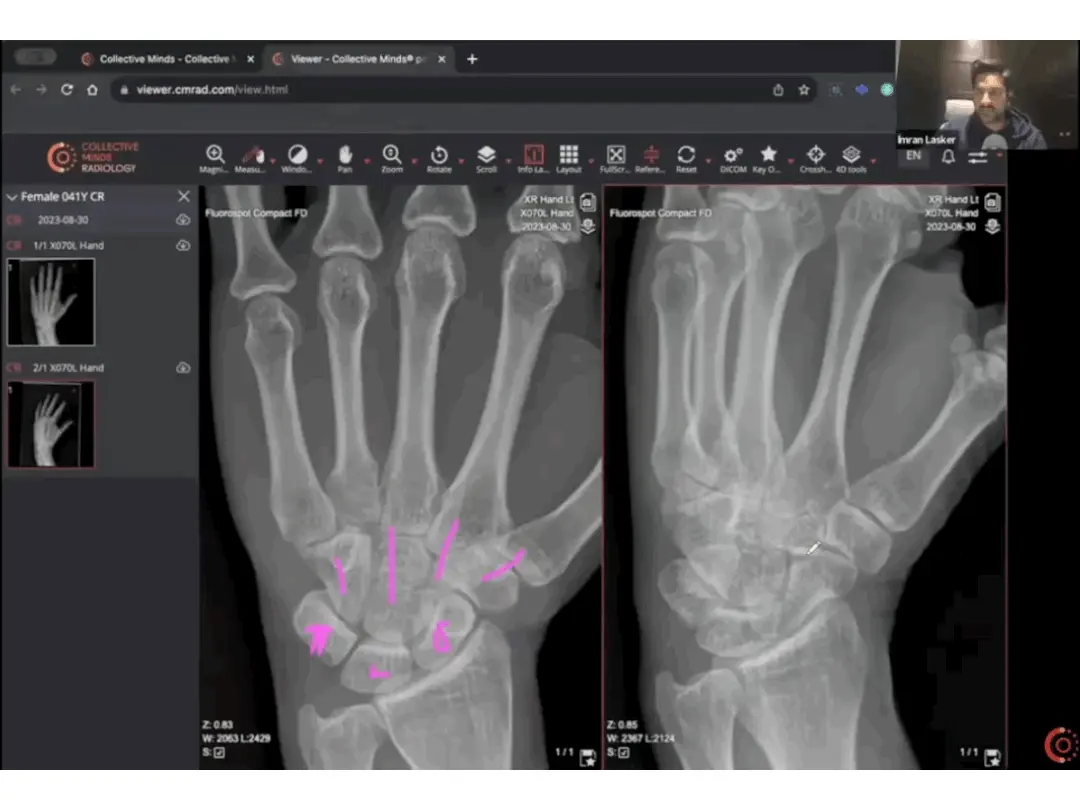

While the essentials and performance features are critical, delightful extras can really set a platform apart. The ability to create and use your own case library is a major plus. A clinical-grade DICOM viewer with advanced teaching tools—like windowing, pointing, measurements, and more—can significantly enhance the learning process.

Creating a fun atmosphere and maintaining a good user experience (UX) is key to keeping learners engaged. The platform should support on-demand peer reviews, re-use content and questions, and display information or videos alongside the DICOM viewer to enrich the learning experience.